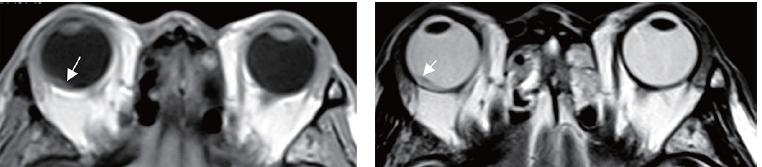

来个眼底病患者,这是什么病呢?拍个片子看看吧。

《眼科CT与MRI学习精要》在身,让行走在江湖的各位小伙伴们不再提心吊胆。

这是我们出品的第6个分册,也是眼科CT与MRI的第2版。